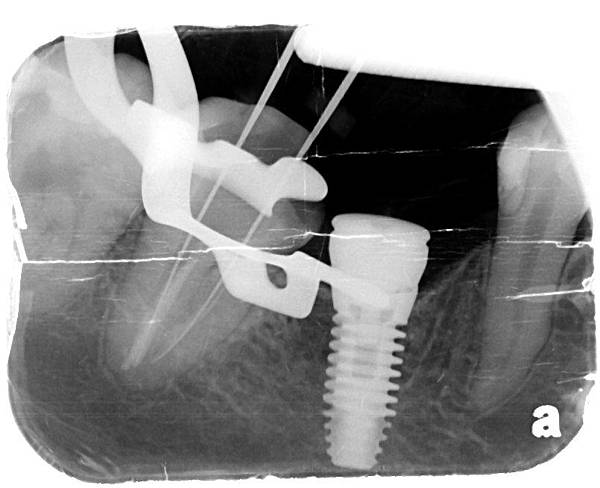

X光片系列

X光片系列

完成圖 X光片系列

X光片系列